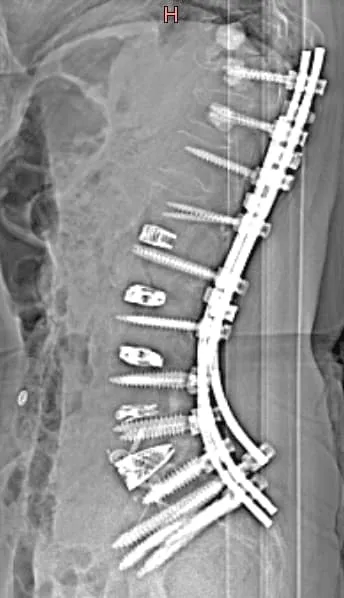

X-ray of a spine with surgical rods and screws implanted along the vertebrae.

90%+ Need Additional Surgery